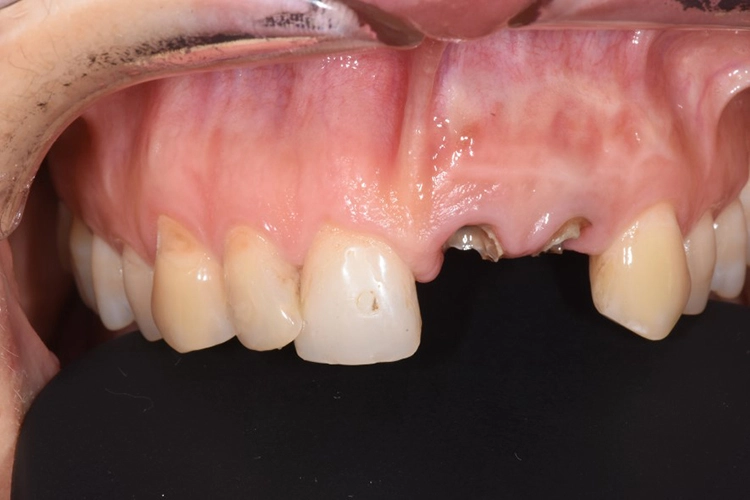

Fall 3: Sofortimplantation

Dr. Blume

Zu unserem Ausgangsbefund zählt die sechs Punkt-Taschenmessung, die Vitalität und Perkussionsprobe sowie ein Röntgenbild. Besonders wichtig ist in diesem Zusammenhang auch die genaue Anamnese des Patienten.

Deutlich auffallend und für die Patientin sehr wichtig war die anatomisch individuelle Zahnstellung des Zahnes 11. Um dem Wunsch der Patientin auf eine für ihr Umfeld unauffällige Behandlung gerecht zu werden, entschieden wir uns gemeinsam für eine Sofortimplantation mit einer provisorischen Sofortversorgung des Implantates. Kein Provisorium kommt der Natur so nah wie die Natur selbst und daher planten wir die Umarbeitung der Zahnkrone 11.